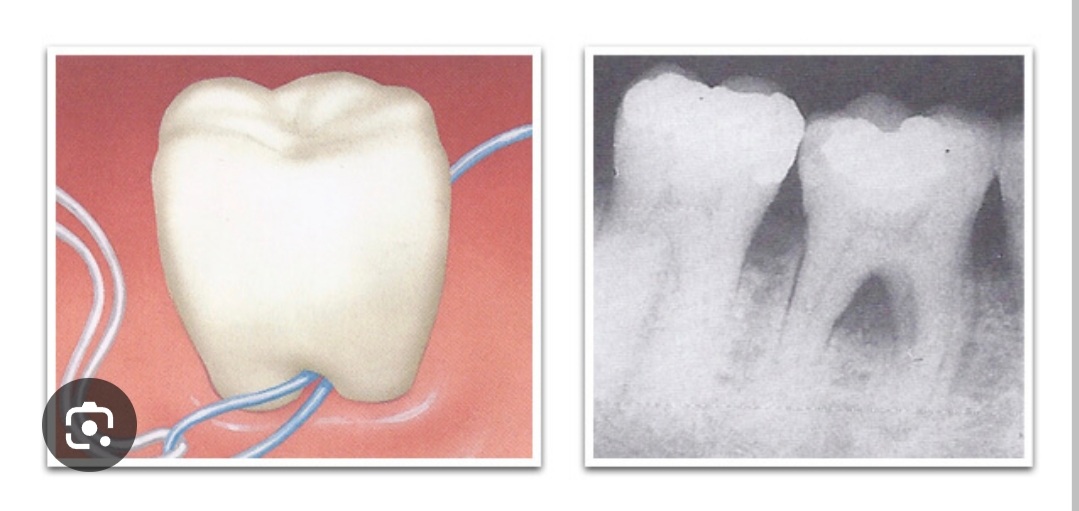

저기가 노출될수가있나??? 트라이앵글존 말하는거면 뿌리가이가 아니라 이빨사이인데 | 24.10.14 11:20 | | |

(IP보기클릭)183.101.***.***

옛날에 치과관련글 검색하다보니 보였어... 잇몸이 내려가 저 사이가 노출된 사람이 있긴한가봐 | 24.10.14 11:21 | | |

치근이개부 병변은 님들 50년 후의 미래이고 절대 드문 질환이 아니라 아주 흔한거니까 예방을 위해 스케일링 꼬박꼬박 받자 | 24.10.14 12:57 | | |

치과 글 보다 보면 노출된 뿌리 안쪽도 닦으란 말이 가끔 보임... | 24.10.14 11:19 | | |

유게이들이 아직 젊고 잇몸 튼튼해서 그렇지 저렇게도 치실 쓰는거 맞다